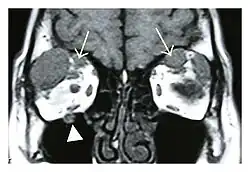

| Mass lesion around the right optic disc in a 44-year-old man with IgG4-related ophthalmic disease and a serum IgG4 of 599 mg/dL.[1] (T2-weighted MRI) | |

The extent of inflammation that can occur in IgG4-ROD is well demonstrated on magnetic resonance imaging (MRI).